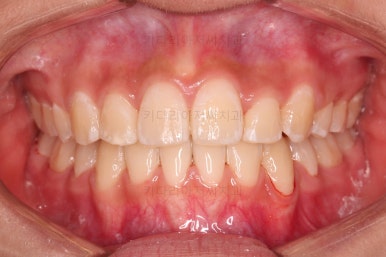

치료 종료시의 모습이에요.

총 21개월 걸렸고요.

발치를 중간에 결정했기 때문에 조금 지체된 면이 없지 않았으나 기간부터 치료 결과까지 만족스러운 치료였습니다.

치여링 가지런해졌고, 교합과 중앙선 등 입안의 모습이 매우 좋아졌어요.

불규칙하게 마모되어 있던 치아의 개별 형태도 약간씩 다듬어 드렸고요.

입매도 본인이 원하는 정도로 만들었고, 웃는 모습, 뻐드러졌던 각도도 매우 잘 개선이 되었네요.

기울어보이던 치열의 경사도 개선이 되었고요.

전반적으로 만족스러운 치료였습니다.